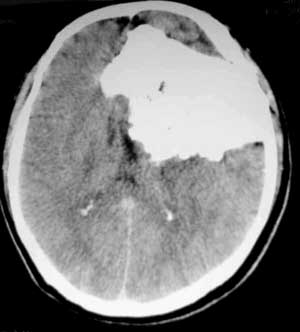

男性,60岁,反复癜痫40余年。

病理结果

骨软骨瘤